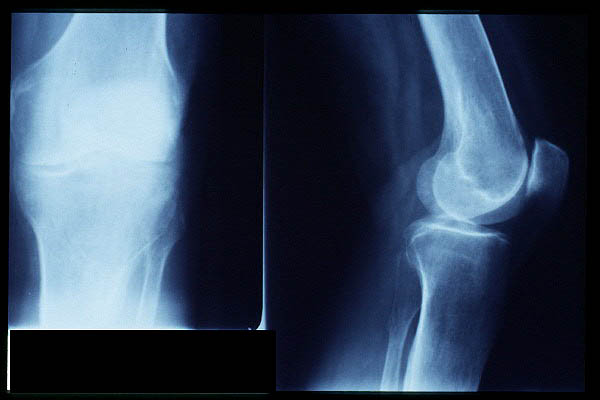

APR Gonartrosis